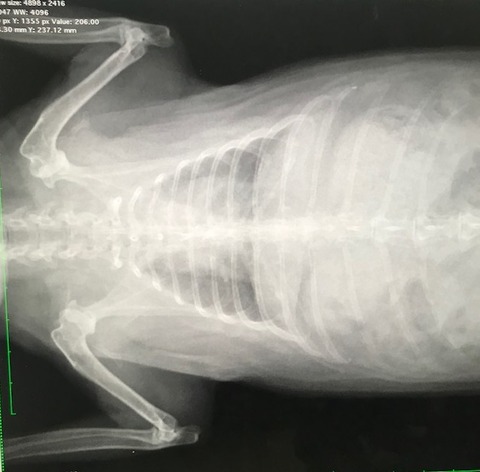

で、お歳、なこともあるのか呼吸の様子も少し気になってたので、

念のためのレントゲンをお願いしました。

胸、お腹、諸々特に問題視する箇所はありませんでした